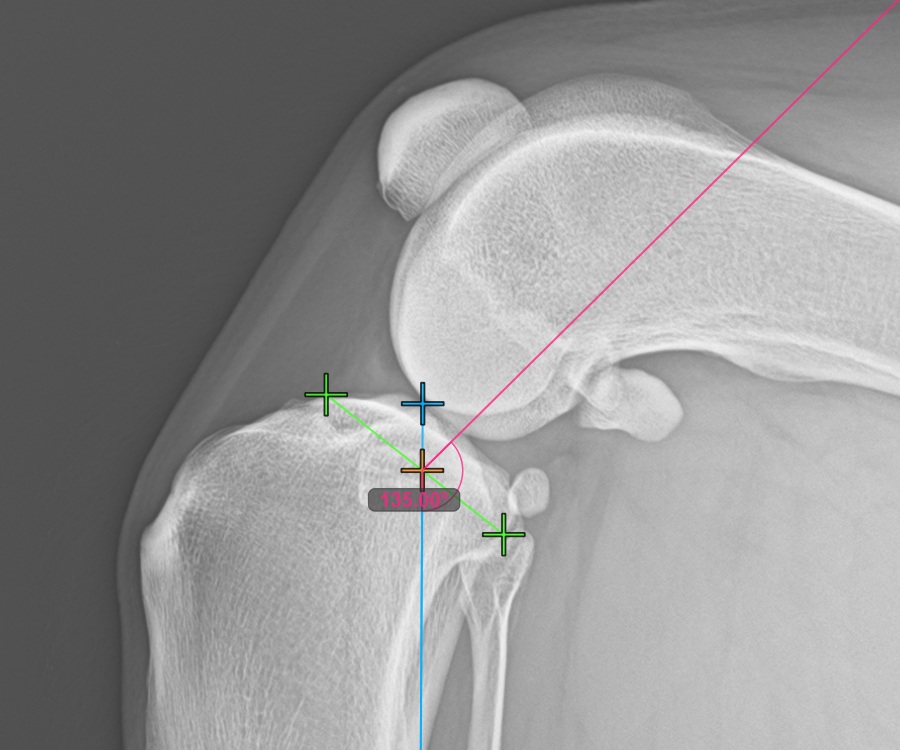

A mérés folytatásához jelölje meg a tibia fejének legcaudalisabb pontját. Ezen felül a szoftver automatikusan létrehoz egy rögzített 135°-os szögmérést, ahol a szög csúcspontja a tibia hosszanti tengelye és a legcranialisabb és legcaudalisabb pontot összekötő vonal metszéspontja.

A lenti kép a tibia plató legcaudalisabb pontjának szokásos elhelyezkedését ábrázolja.